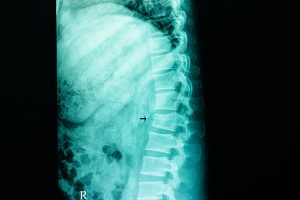

According to the Cleveland Clinic, a compression fracture is a small break in the vertebrae, which are the bones that wrap around your spinal cord to protect it. Unlike a full break, a fracture may be very small or even a hairline. Yet, these fractures are dangerous because they cause the bone to become significantly weaker. Over time, the bone can weaken so much so that it collapses, often leading to changes in spinal shape and function.

Typically, compression fractures from car accidents occur in the upper portion of the back, which is the thoracic region. However, they can extend downward and impact any of the bones along the spinal column. No matter where they occur, they often lead to injury, long-term damage, and sometimes, pain.